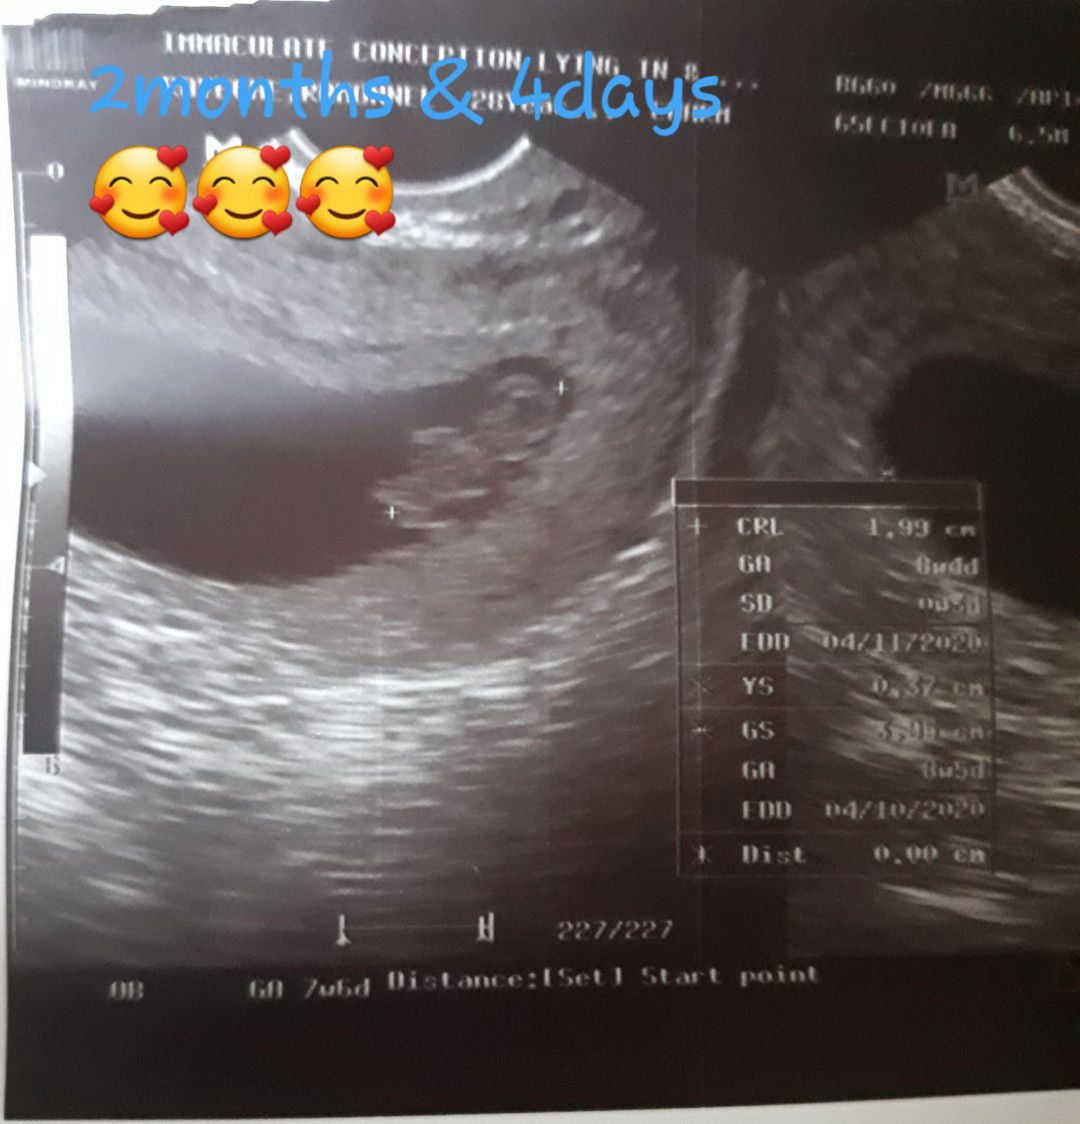

thanks much SA hubby ko sa pgiging sObrang sOpportive SA pregnancy ko ???bAsta di ko mawari ung Saya n sinamhan nya Ko pra mgpa transvaginal ultrasound... last week nunG cnbi ko Sa knya n my sched aq Sept 4 pra sa ultrasound ngulat aq sa nGing sAgot nya "cge babe mgabsent po aq pra msAmhan kita" nunG una aKla ko biro lng or mkklimutAn nya ???pero OMG Sept 4 ng umaga aNg aga nyang ngising ngluto ng almusal akala ko ppsok sYa sabay gising nya skin sAby tnong kung aNong oras ung sched ko ???gulat p ko pero deep inside sObrang kinilig aq ??gnito pla aNg feeling ng my supportive kNg aSawa... even though n every other day uwi nya sObrang pinprmdaM nya sakin at sa bby nmin kung paano nya kmi alagaan at gwing priority above anything else ???thank you papa G kc sYa ung binigay nyo pra sakin at sa mGiginG bby nmin...aNg kulit p nmn nya hbng ngllkAd kmi pAulit ulit n tintnong if IlNg months n c bby, ehhh aNg pgkkaalm ko 7 weeks p lng pro sa ultrasounds 2months and 4days n sYa nrmal din unG heartbeat ni bby 160bmp per minute ??sObrang Saya ni hubby nunG NkitA nya mismo ung heart beat ni bby ??SAna hndi mgbgo c hubby ???love n love k nmin ni papa bby ??